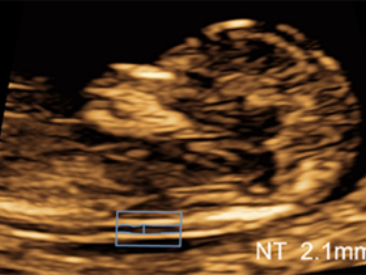

Klinik G?rĂŒntĂŒler